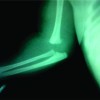

We present a case of an 8-day-old neonate who presented to the outpatient clinic with swelling and deformity over the right elbow, left elbow, and left knee. The child was born full-term, through normal vaginal route and the delivery was uneventful. The child cried immediately after birth and started breastfeeding during the 1st h of delivery. The child was discharged under satisfactory conditions and no bony abnormality or abnormal attitude of the limb was noted at the time of discharge. On performing radiographs (Fig. 1) and ultrasonographic examination (Fig. 2) of both the upper and lower limbs, the patient was diagnosed with bilateral distal humeral physeal separation with the left proximal tibia physeal injury.

Although unsure, the etiology of multiple fractures at this age was considered most likely to be “birth-related trauma”. The patient’s injuries were managed conservatively by minimal traction application and splinting the limbs in a cuff and collar sling. At 4 weeks follow-up, there was evidence of fracture healing present with bridging callus formation with no further complaints. Three months later, the child was brought to the outpatient clinic for follow-up when swelling and abnormal posture of the right knee was observed. Antero-posterior (AP) and lateral radiographs (Fig. 3d) of the right knee revealed a fracture right proximal tibia and fracture mid-shaft right fibula, with healing callus formation present.